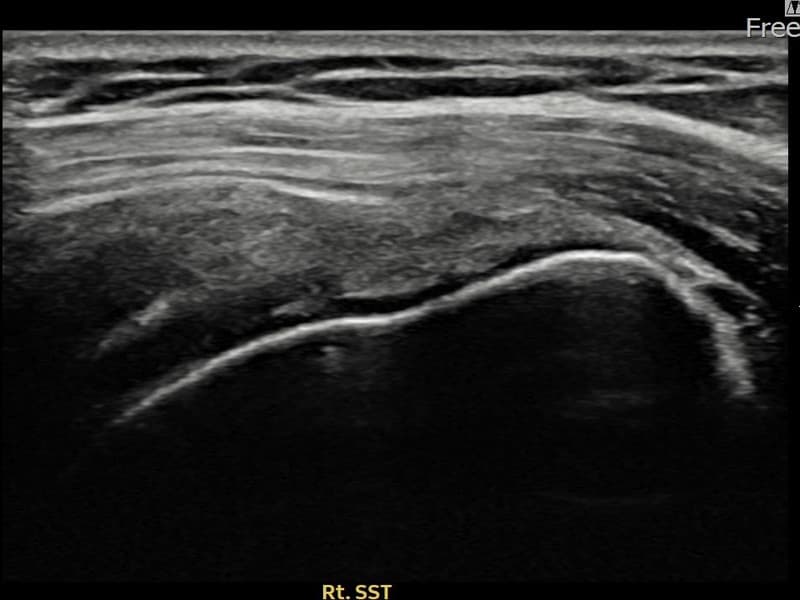

After

시술 전 초음파 측정 결과 파열 크기는 12mm × 4mm (힘줄 두께의 약 48% 결손)로 확인되었습니다. 시술 전 초음파에서 우측 극상근건 관절면측의 에코 단절과 힘줄 두께 감소가 확인되었습니다. 시술 후 초음파에서 힘줄 연속성이 회복되고 에코 패턴이 균질하게 개선된 것이 관찰되었습니다.

40대 후반 여성 환자분으로, 아이 돌봄과 집안일을 도맡아 하시며 어깨를 반복적으로 사용하다 통증이 생겨 내원하셨습니다. 처음에는 무거운 물건을 들 때만 아팠으나 점차 팔을 수평으로 올리는 것 자체가 어려워진 상태였습니다. 초음파 검사에서 우측 극상근건 관절면측 부분파열이 확인되었으며, 비수술 축소봉합술로 치료 계획을 수립하였습니다. 시술 당일 귀가하셨고 보조기 착용 4주, 이후 단계적 재활을 진행하였습니다. 시술 14주 후 추적 초음파에서 힘줄 연속성이 완전히 회복된 것이 확인되어 통증 없이 일상 복귀에 성공하셨습니다.